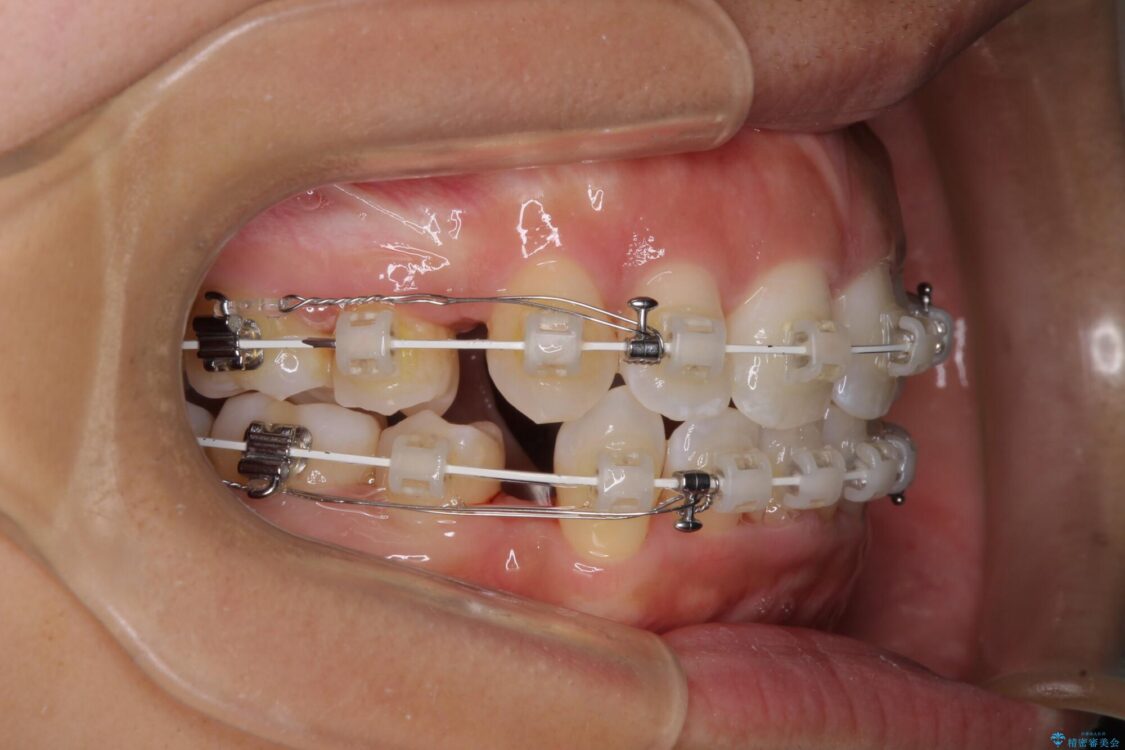

治療途中

• 抜歯矯正で唇を閉じやすく 目立たないワイヤー装置 治療途中画像